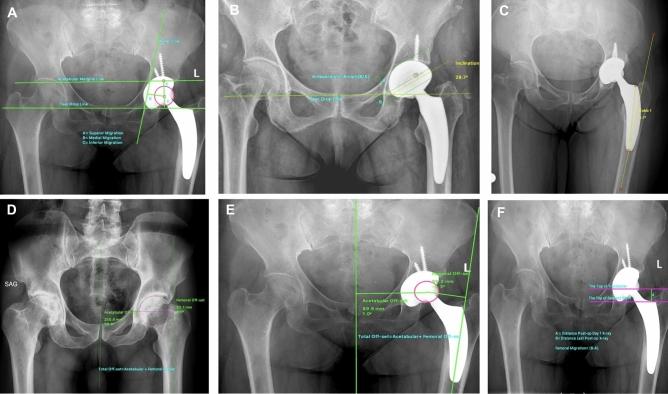

This study aims to answer the question: Which are superior-conventional or short femoral stems?. An Optymis stem was used as a short-femoral stem, and an Accolade II stem was used as a conventional-femoral stem. There were 95 patients in the short femoral stem group (Group 1) and 90 in the conventional stem group (Group 2). The SF-36 Life Quality Score, thigh pain, and the Harris Hip Score were used to evaluate the patients' clinical outcomes. Pre-operative, immediate post-operative, and final follow-up x-rays were used for radiological evaluation. Stem varus/valgus alignment, hip offset changing, acetabular anteversion/inclination changing, femoral migration, acetabular migration, periarticular ossification, and osteointegration evaluation were assessed for both groups. The mean follow-up time was 5.5 years for Group 1 and 5.2 years for Group 2. No significant difference existed between the two groups in terms of clinical scores (Harris Hip Score, SF-36). Thigh pain was significantly higher in Group 2 (p = 0.0001). As for radiological parameters, Group 1 exhibited more varus position-related results. In terms of angular stability, Group 1 was found to be more unstable than Group 2 (p = 0.0001). The power to reconstruct femoral offset was superior in Group 1. Periarticular ossification was more frequent in Group 2. Femoral osteointegration was denser proximally in Group 1 and distally in Group 2. When mid-term radiological and clinical results of both femoral stems are evaluated, they have no superiority over each other.

传统股骨柄与短柄相比,哪种更优越?使用 Optymis 短柄作为短柄组,Accolade II 股骨柄作为传统股骨柄。短柄组 95 例(组 1),传统柄组 90 例(组 2)。采用 SF-36 生活质量评分、大腿疼痛和 Harris 髋关节评分评估患者的临床疗效。采用术前、术后即刻和最终随访 X 线片进行影像学评估。评估两组患者的股骨柄内翻/外翻、髋关节中心外移变化、髋臼前倾角/倾斜度变化、股骨迁移、髋臼迁移、关节周围骨化和骨整合情况。组 1 的平均随访时间为 5.5 年,组 2 为 5.2 年。两组临床评分(Harris 髋关节评分、SF-36)无统计学差异。组 2 的大腿疼痛明显高于组 1(p=0.0001)。在影像学参数方面,组 1 表现出更多的内翻位置相关结果。在角度稳定性方面,组 1 比组 2更不稳定(p=0.0001)。组 1 重建股骨偏心距的能力更强。组 2 关节周围骨化更常见。组 1 股骨近端骨整合更密集,组 2 股骨远端骨整合更密集。当评估两种股骨柄的中期影像学和临床结果时,它们彼此之间没有优势。